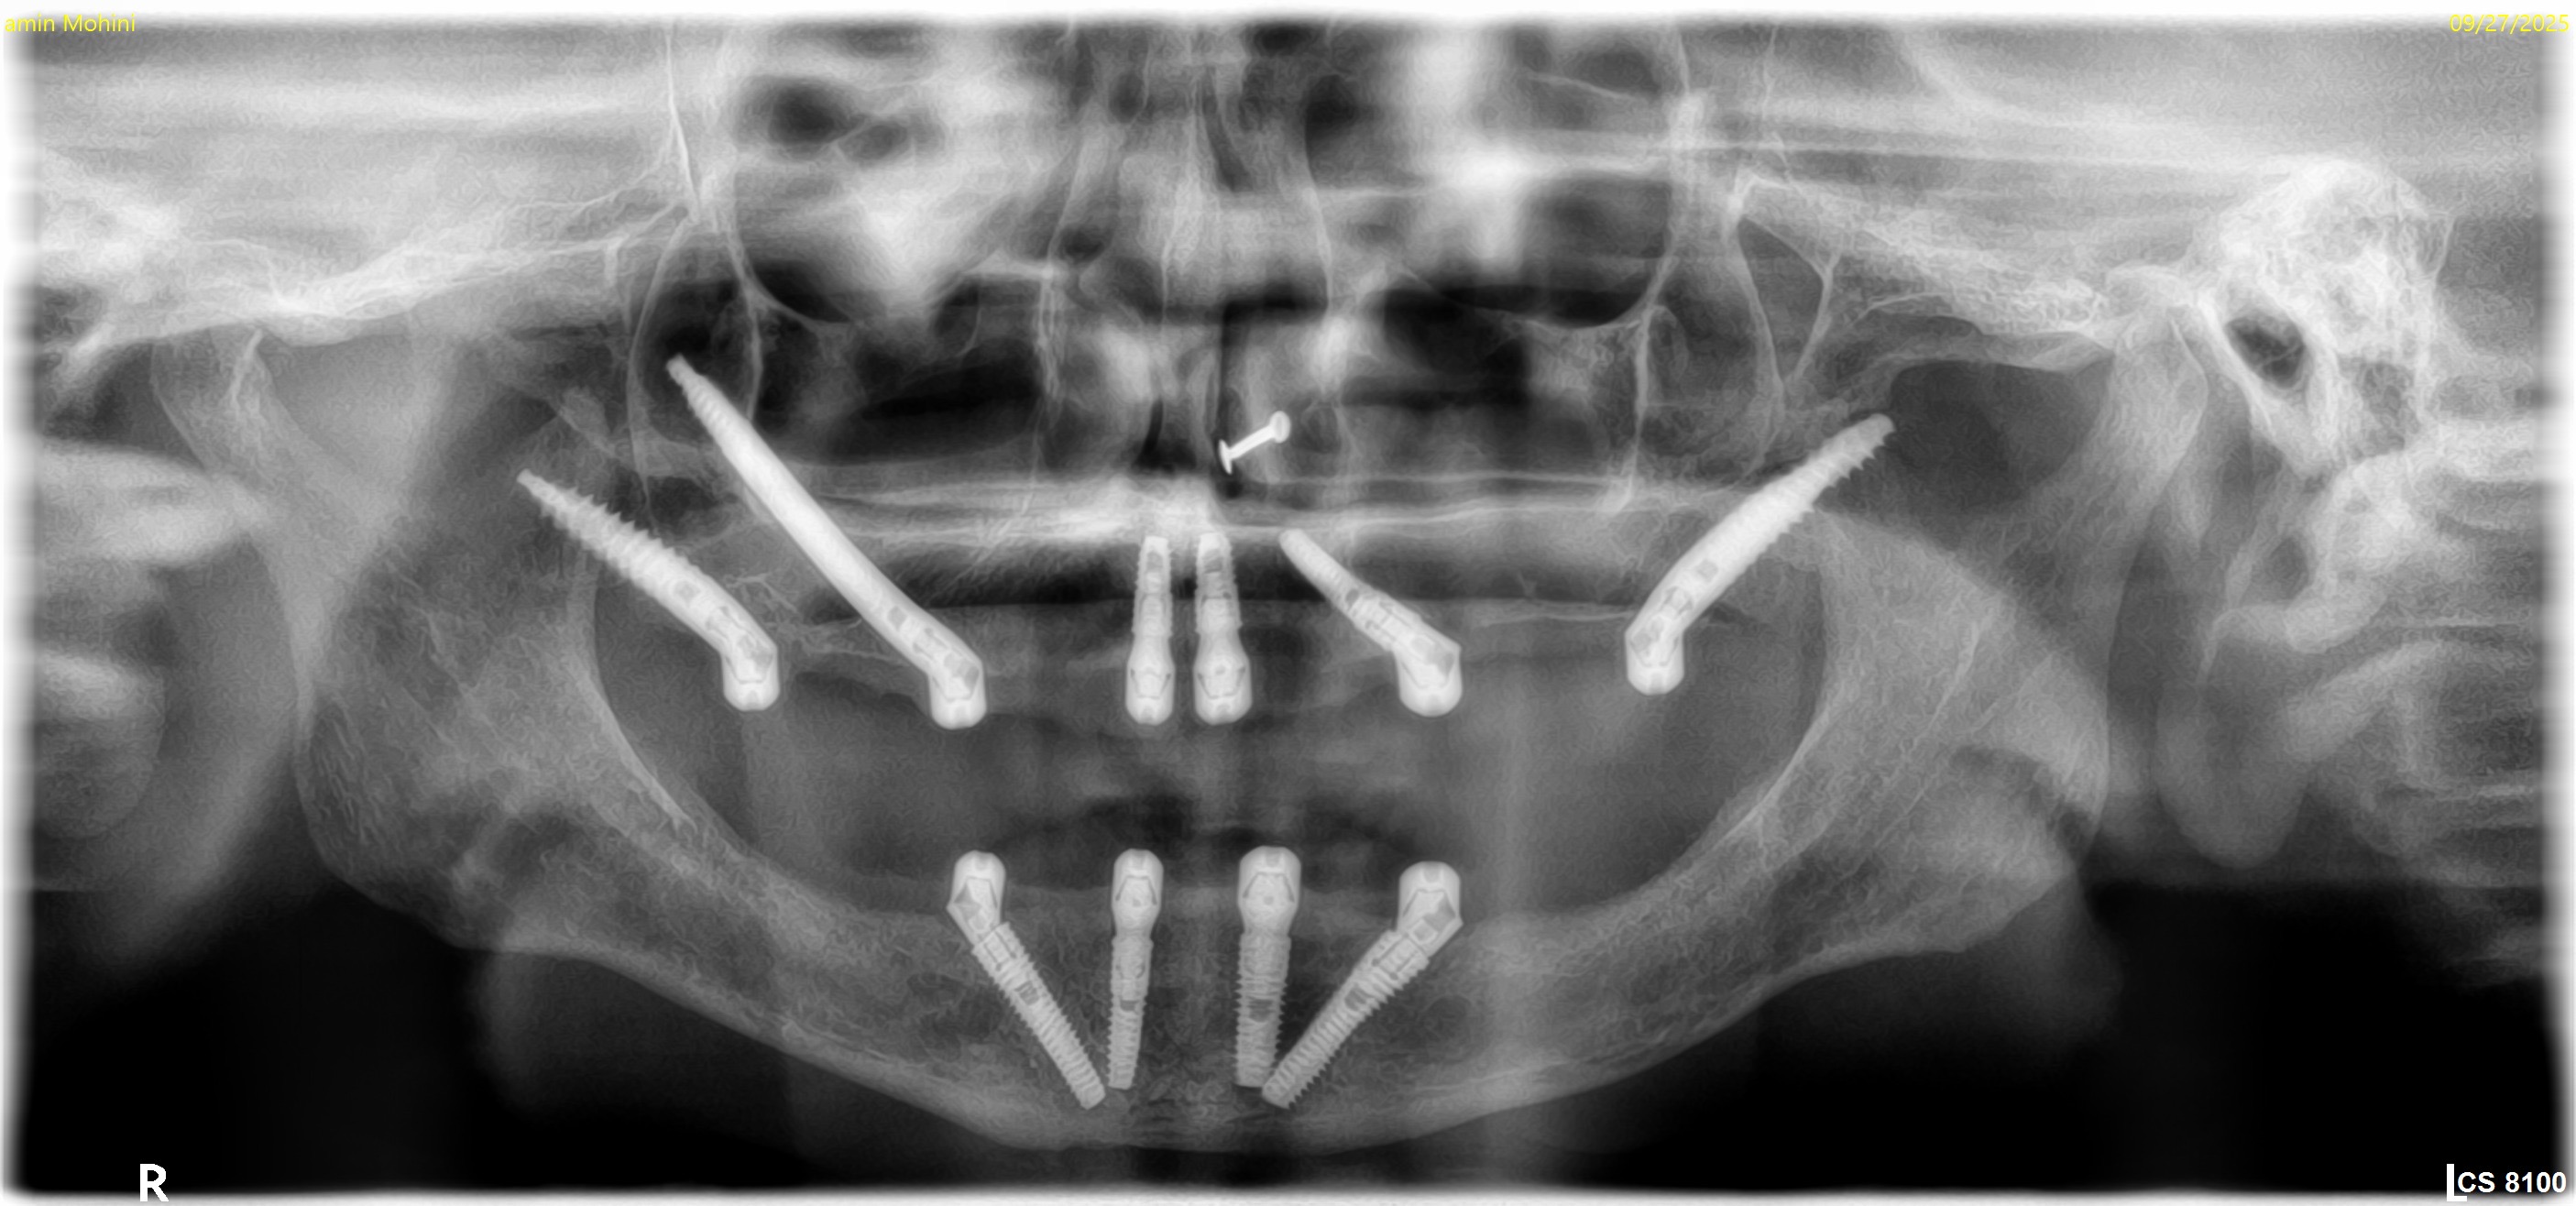

Brush your teeth twice a day with a soft-bristled toothbrush and toothpaste made for implants. Floss daily with unwaxed tape or implant-specific floss. Be careful when brushing and flossing around the implant.